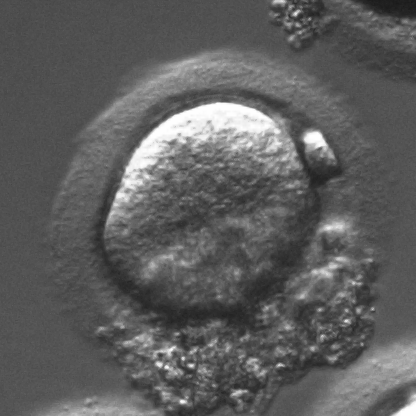

Infertility is becoming an issue for an increasing number of couples. The most common solution, in vitro fertilization, requires embryologists to carefully examine light microscopy images of human oocytes to determine their developmental potential. We propose an automatic system to improve the speed, repeatability, and accuracy of this process. We first localize individual oocytes and identify their principal components using CNN (U-Net) segmentation. Next, we calculate several descriptors based on geometry and texture. The final step is an SVM classifier. Both the segmentation and classification training is based on expert annotations. The presented approach leads to a classification accuracy of 70%.